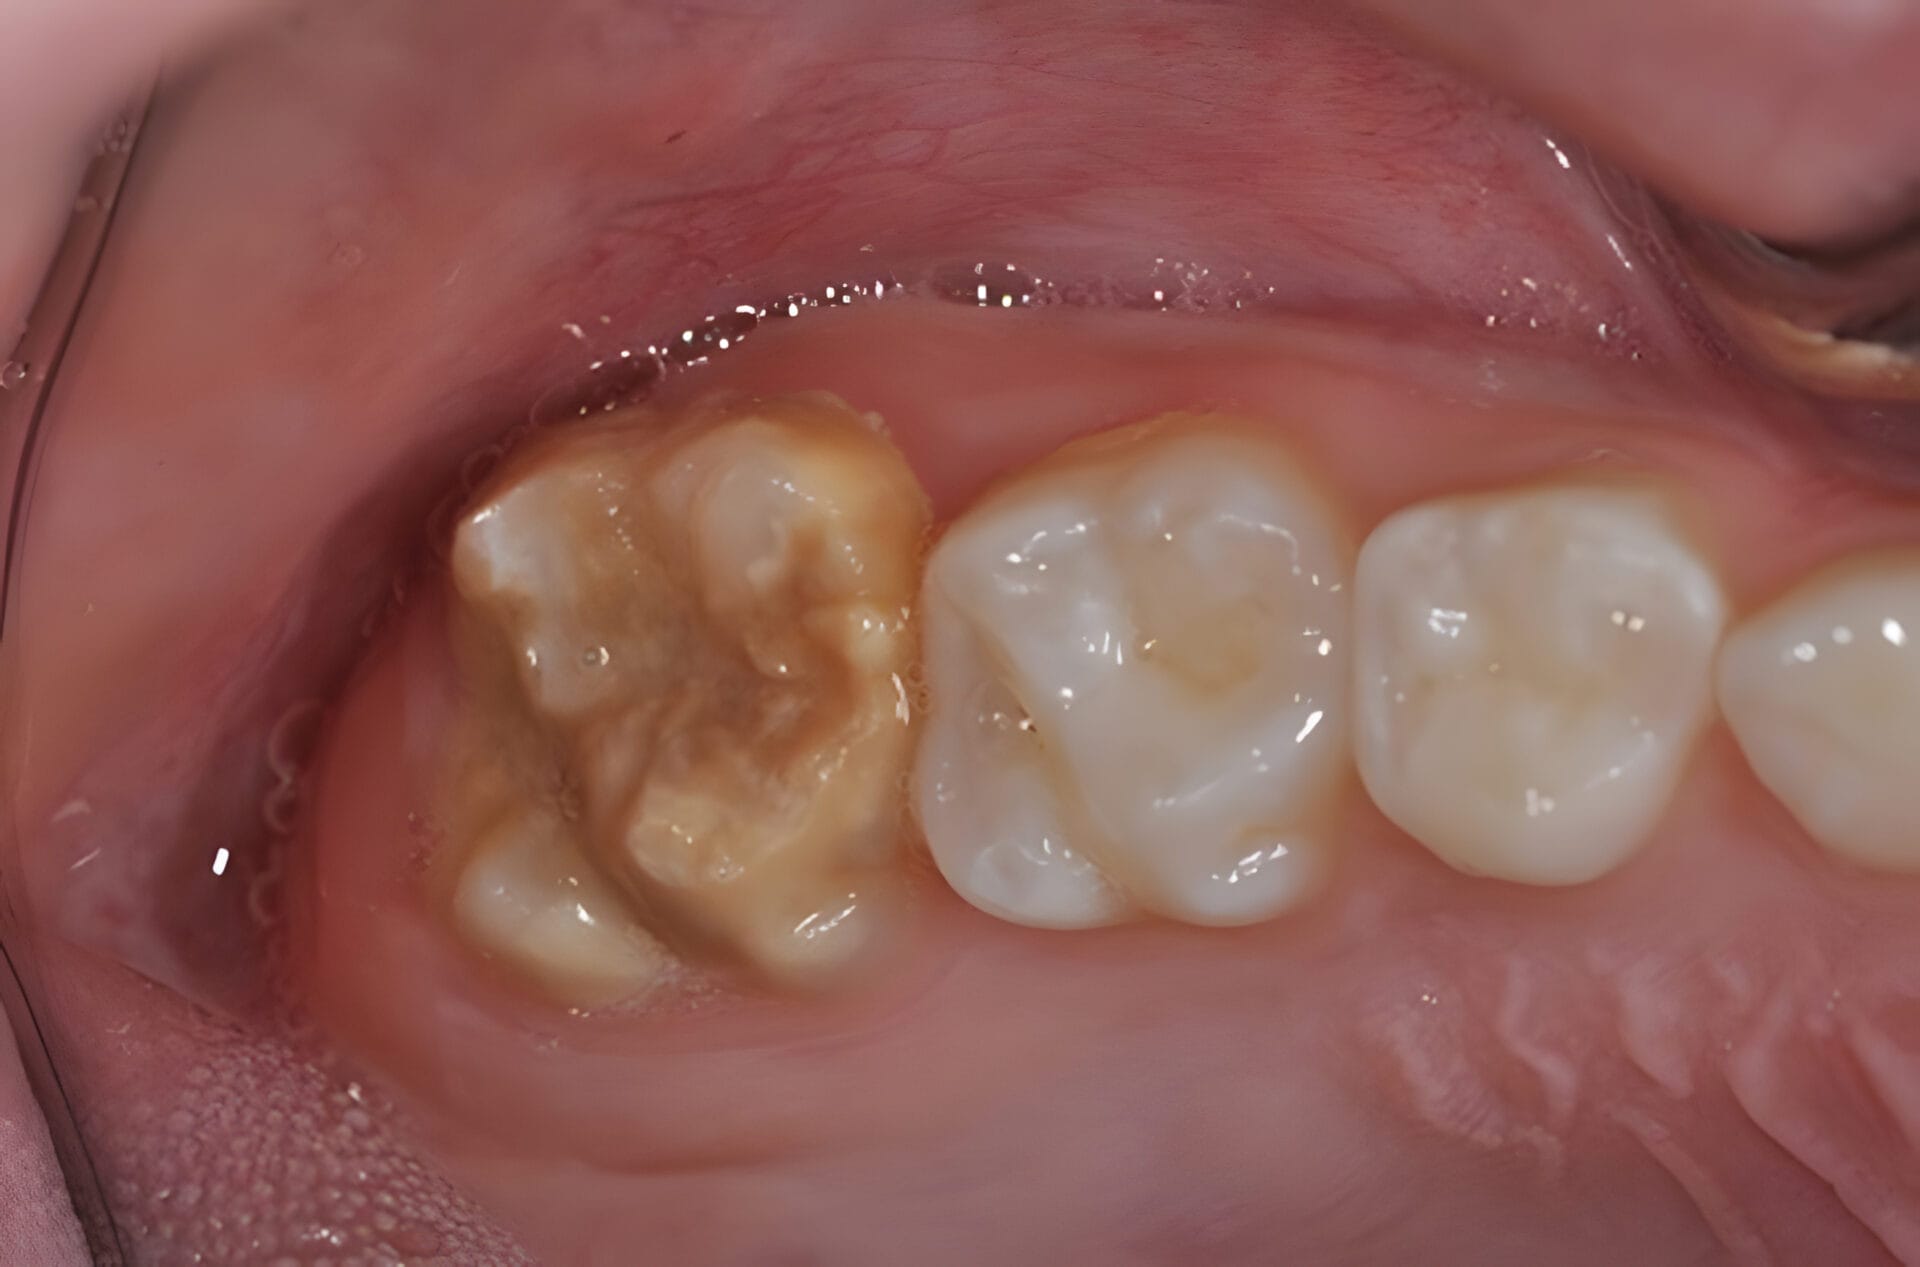

Kreidezähne, auch Molaren-Inzisiven-Hypomineralisation (MIH) genannt, sind eine Zahnschmelzbildungsstörung. Dabei ist der Zahnschmelz unzureichend mineralisiert, wodurch er weicher, poröser und bruchanfälliger wird. Betroffen sein können sowohl das bleibende Gebiss als auch das Milchgebiss. Typisch sind umschriebene, weissliche bis gelblich-bräunliche Verfärbungen. Der geschwächte Schmelz kann leichter ausbrechen und die Zähne reagieren oft empfindlich.

- Flecken/Verfärbungen (weiss, gelb, braun) mit klaren Rändern

- Rascher Substanzverlust: Schmelz bricht beim Kauen oder Putzen ab